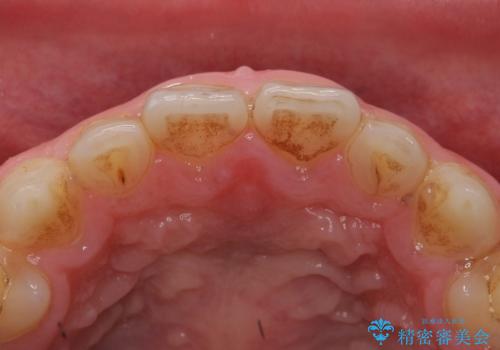

矯正を途中でやめてしまったとのことで、歯に矯正の接着材が残っており着色も顕著でした。

奥歯の咬合面にはレジンが盛られた状態でした。